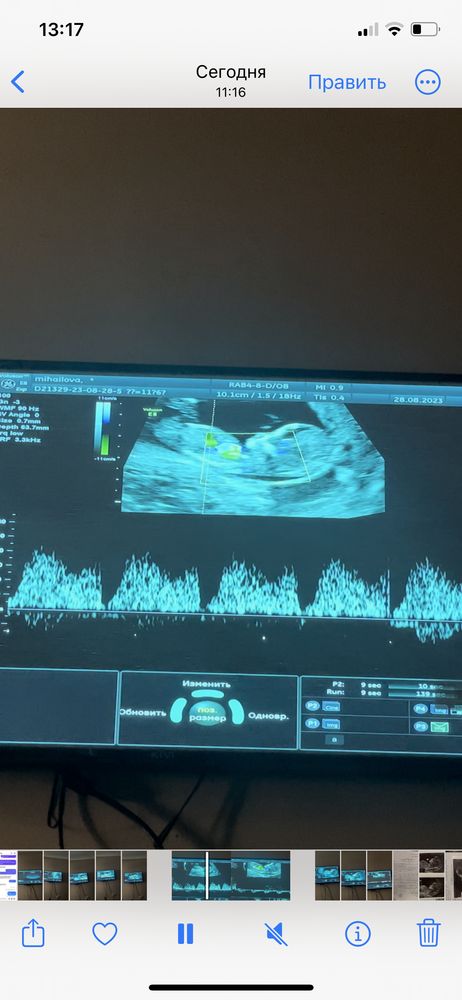

Генриетта , а вот здесь можно посмотреть по половому бугорку, тут у вас тоже похоже на девочку.

Евгения, прикол 🙈 я думала мальчик хахахах но это видимо пупок там 🤣🤣🤣

но там вообще крошечное всё 🙈